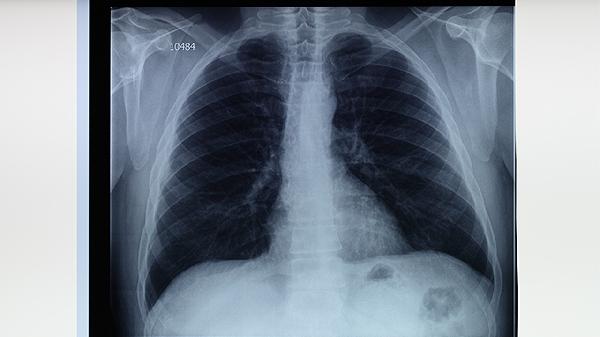

肺部或縱隔腫瘤可能壓迫或侵犯肺動脈,導(dǎo)致血管壁受損并形成肺動脈瘺。腫瘤引起的肺動脈瘺可能伴隨體重下降、乏力、咯血等癥狀,需通過影像學(xué)檢查明確診斷。